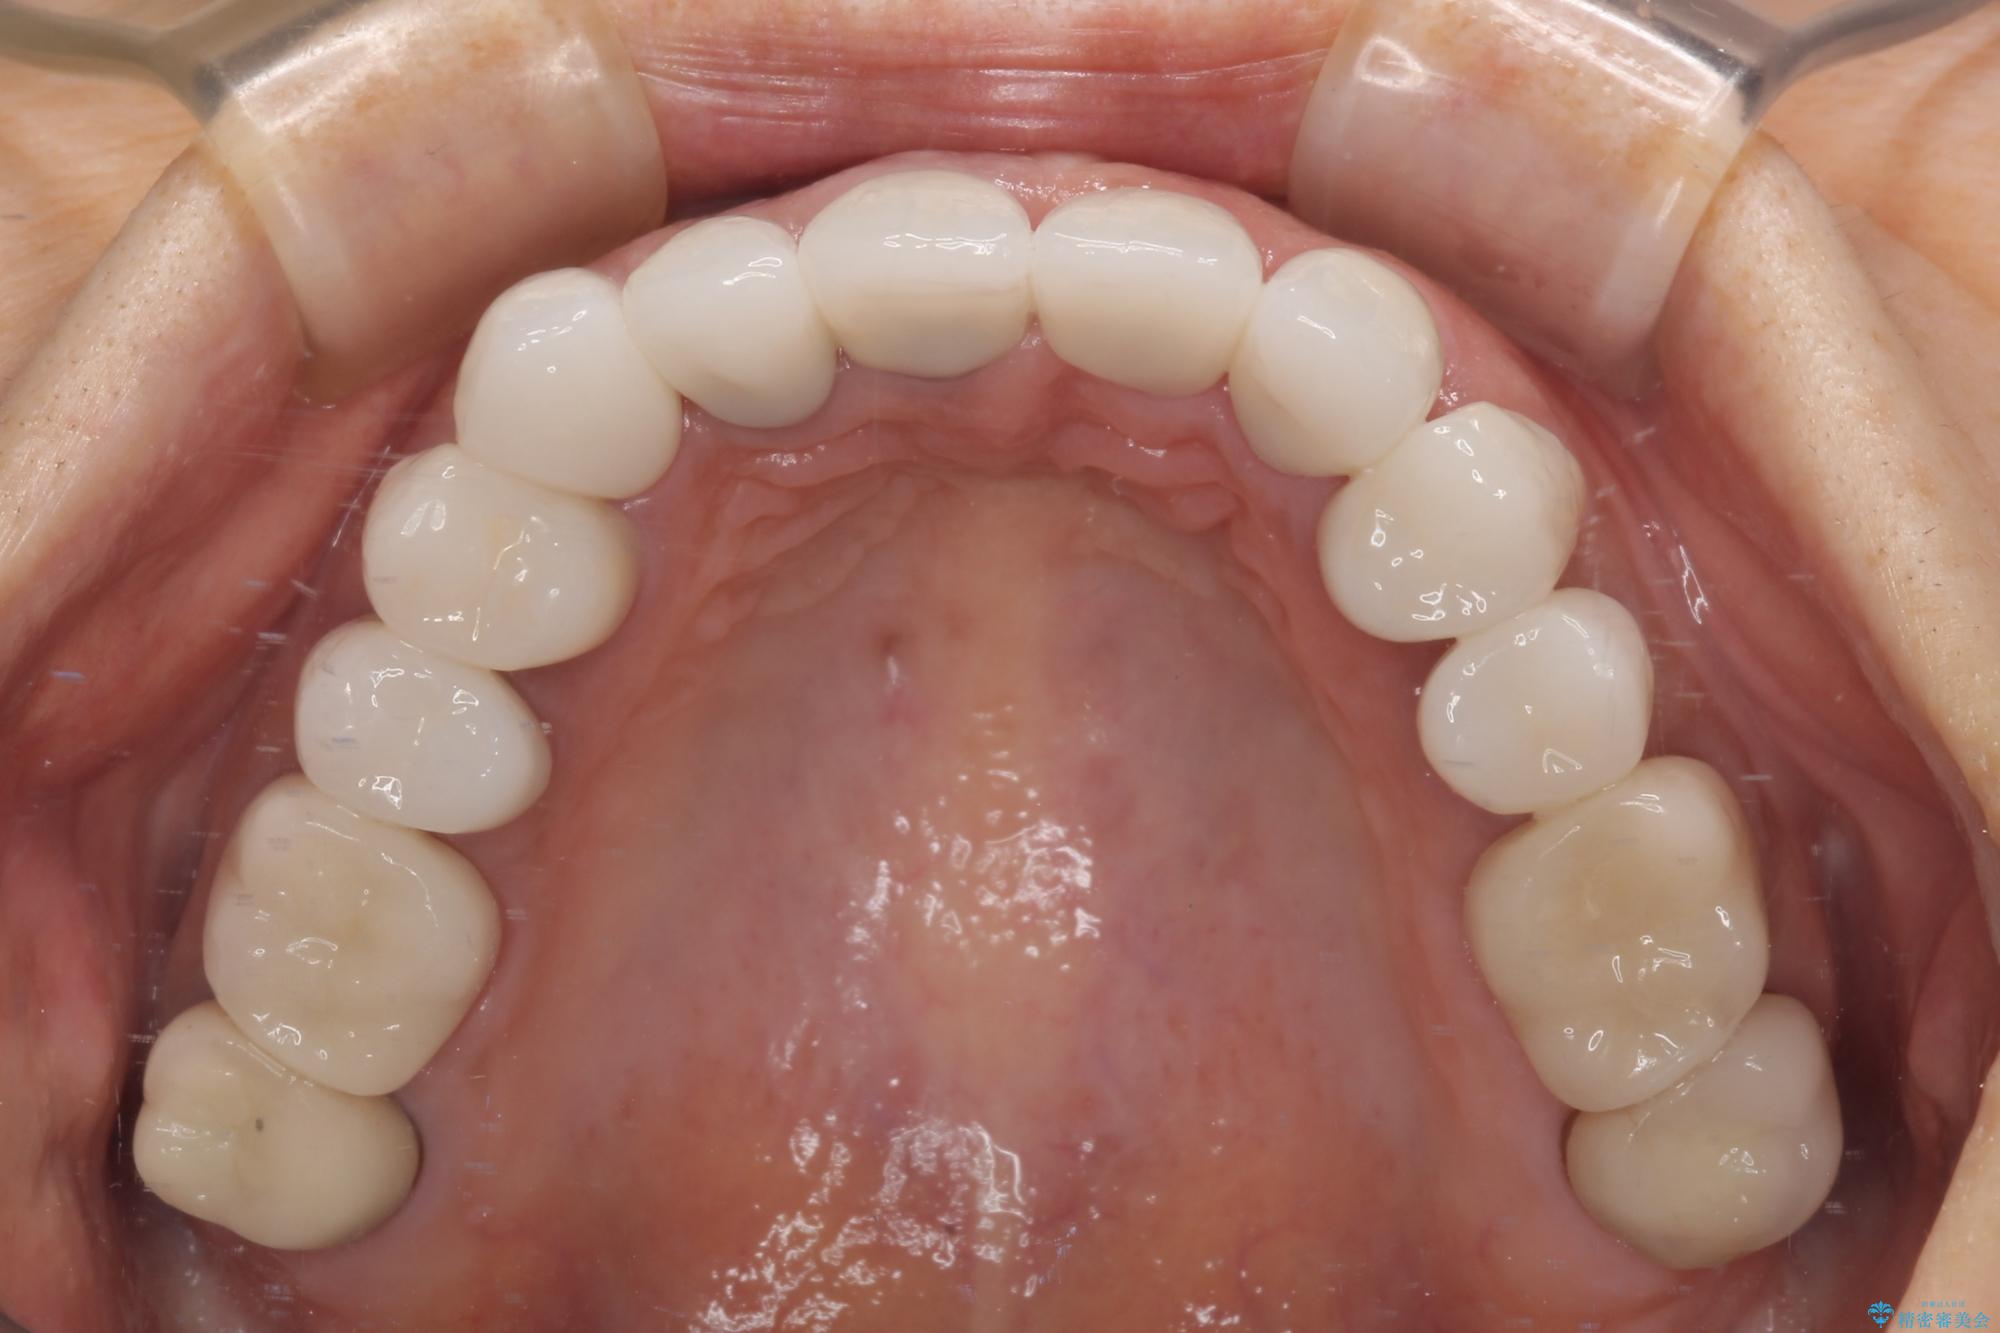

20年以上前から、むし歯になったり詰め物が欠けたりする度に部分的に処置を行ってきたそうですが、この際統一感のある前歯にしたいとのことで、上顎前歯9本をオールセラミッククラウンによる補綴治療を行うこととしました。

色調が統一されるだけでなく、歯肉ラインに見えていた茶色の境目も綺麗に改善されました。